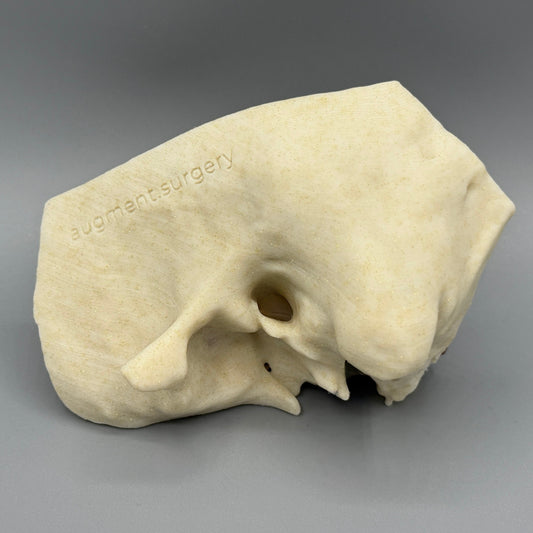

Plant-based surgical simulators made in the U.S.A.

Dissect each one to learn human temporal bone anatomy, hearing and vestibular systems.

Delta-Left OpenEar 3D Temporal Bones

Regular price $74.00 USDRegular priceUnit price per -

Delta-Right OpenEar 3D Temporal Bones

Regular price $74.00 USDRegular priceUnit price per -